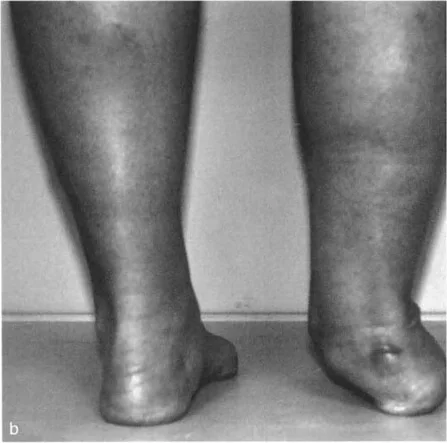

تغير شكل القدم والكاحل

• تشوه مرئي: في كثير من الحالات، يكون التشوه واضحًا للعين المجردة. قد يظهر الكاحل منحرفًا إلى الداخل (تقوس) أو إلى الخارج (روحبة).

• تشوه التقوس (Varus): يبدو الكاحل والقدم منحرفين إلى الداخل، مما يجعل القدم تبدو ذات قوس عالٍ (قدم جوفاء). هذا يسبب ضغطًا زائدًا على الحافة الخارجية للقدم.

• تشوه الروحبة (Valgus): يبدو الكاحل والقدم منحرفين إلى الخارج، مما يؤدي إلى تسطح قوس القدم (قدم مسطحة مرنة). هذا يزيد الضغط على الجانب الخارجي لمفصل الكاحل.

• تغير في شكل القدم: تتكيف القدم مع تشوه الساق للحفاظ على استواء السطح السفلي على الأرض. في تشوه التقوس، قد تصبح القدم صلبة وذات قوس عالٍ. في تشوه الروحبة، قد تتسطح القدم وتصبح مرنة.

* المعاينة البصرية: ملاحظة شكل الساق والقدم والكاحل أثناء الوقوف والمشي. يتم تقييم العرج، وتوازن الجسم، وكيفية توزيع الوزن.

* تقييم تعويضات القدم: يتم تقييم كيف تحاول القدم تعويض التشوه في الساق. على سبيل المثال، في تشوه التقوس الساقي، قد تظهر القدم بقوس عالٍ وصلب. في تشوه الروحبة، قد تظهر القدم مسطحة ومرنة.